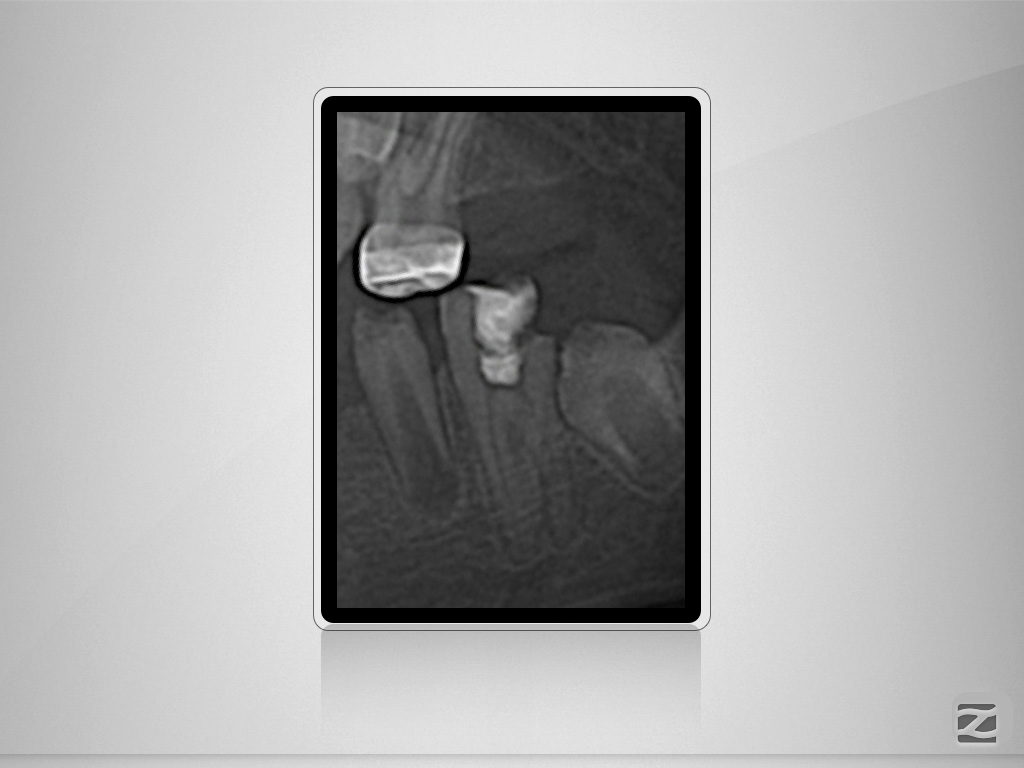

36D.001

Wie wäre es ohne DVT?